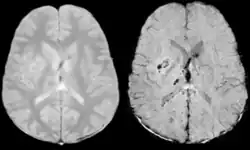

Diffusion weighted imaging offers a powerful means to detect acute stroke. Although it is well known that gradient echo imaging can detect hemorrhage, it is best detected with SWI. In the example shown here, the gradient echo image shows the region of likely cytotoxic edema whereas the SW image shows the likely localization of the stroke and the vascular territory affected (data acquired at 1.5 T).

The bright region in the gradient echo weighted image shows the area affected in this acute stroke example. The arrows in the SWI image may show the tissue at risk that has been affected by the stroke (A, B, C) and the location of the stroke itself (D). The reason that we are able to see the affected vascular territory could be because there is a reduced level of oxygen saturation in this tissue, suggesting that the flow to this region of the brain could be reduced post stroke. Another possible explanation is that there is an increase in local venous blood volume. In either case, this image suggests that the tissue associated with this vascular territory could be tissue at risk. Future stroke research will involve comparisons of perfusion weighted imaging and SWI to learn more about local flow and oxygen saturation.